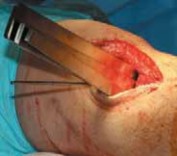

2. The incision lies 2 to 3 cm posterior to the tibial tubercle and 1 cm distal to the joint line, and extends distally for 5 to 6 cm (

TECH FIG 2A

).

2. The incision is taken down through the skin and subcutaneous tissues, revealing the sartorius fascia (

TECH FIG 2B

1. The superior border of the gracilis hamstring tendon is palpated, and the sartorius fascia is opened along the superior border of the gracilis tendon.

2. Medially, the pes bursa is released from the medial tibial tubercle in an inverted L fashion.

3. The pes bursa is carefully elevated distally, taking great care to develop the plane between the bursa and the underlying medial collateral ligament.

4. Proximally, the retinaculum and layer 1 of the knee are incised to the approximate level of the joint line (

TECH FIG 2C